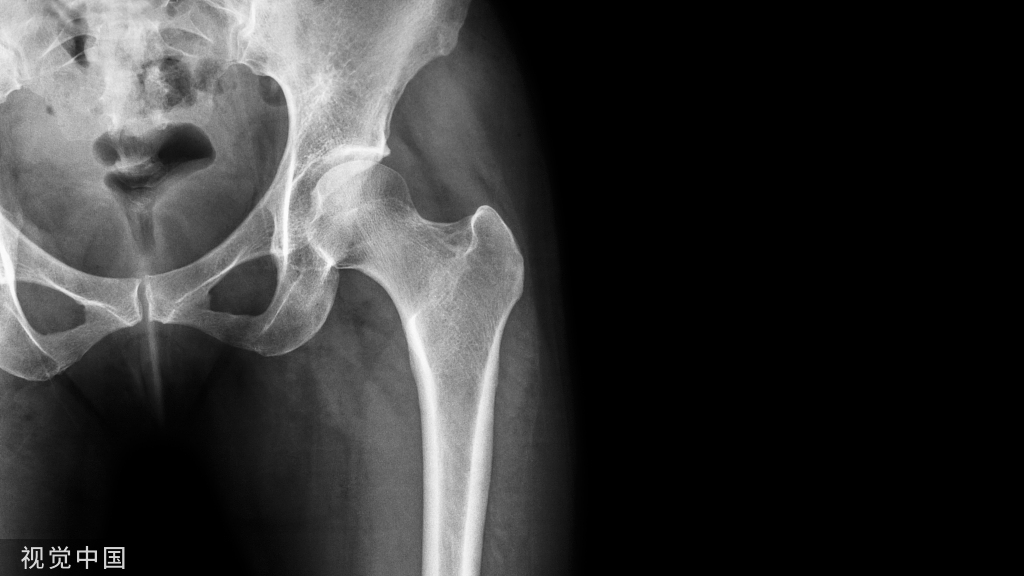

黄韧带主要由弹性纤维和结缔组织构成,覆盖于椎管的后壁,从上椎板的一半呈叠瓦状覆盖下椎板的上半部分,它被认为是维持脊柱内在稳定性、控制椎间运动、并维持硬脊膜后部表面光滑的重要结构,韧带的异位骨化便是黄韧带骨化(OLF)。因胸椎椎管较颈椎及腰椎更为狭小,脊髓和神经根紧贴其中,骨化的黄韧带常导致缓慢进展的脊髓神经功能损害,出现如下肢感觉和运动功能障碍,病理征阳性,反射亢进等临床症状。1920年,Polgar首次报道了胸椎黄韧带骨化(TOLF)与胸脊髓病密切相关。据文献报道,TOLF常发生于亚洲人群,日本人群中的发病率约为36.0%,中国人群中的发病率约为3.8%,在高加索人、非洲人、阿拉伯人等人群中也时有报道。TOLF好发于下胸段,T10~11和T11~12出现率最高,其患病率随年龄的增长而增加,据报道,50~59岁年龄组的患病率最高。Kuh等根据黄韧带骨化物的CT轴位骨窗下的位置和形态将TOLF分为:(1)单侧型:即单侧OLF;(2)双侧型:双侧均存在骨化,但两侧未融合;(3)桥接型:双侧骨化黄韧带相互融合。TOLF患者一旦出现临床症状,手术减压通常是惟一有效的治疗手段,手术方式以经后路椎管后壁切除减压为主,包括整块椎板切除术、分层椎板切除术、椎板成形术等,其中“揭盖式”椎管后壁整块切除法在临床上应用广泛,但存在神经牵拉损伤,术后脑脊液漏等风险,近年来随着脊柱微创手术的发展,涌现了一批如单通道内镜下可视环锯减压术、经皮内镜下后路减压术、单侧双通道内镜减压术,以及计算机辅助导航技术等新型技术。然而,TOLF患者术后并发症及神经功能恢复情况不尽相同,笔者对TOLF患者术后预后相关风险因素进行如下综述。